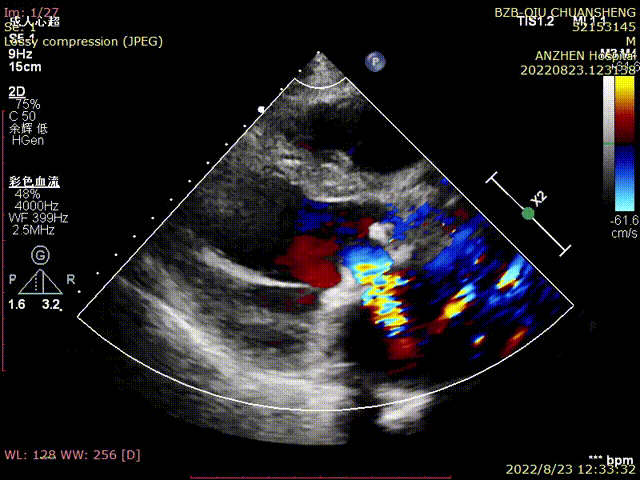

TTE-各大瓣膜反流(CDFI)

TTE-左室长轴-二尖瓣生物瓣+主动脉瓣生物瓣(CDFI)